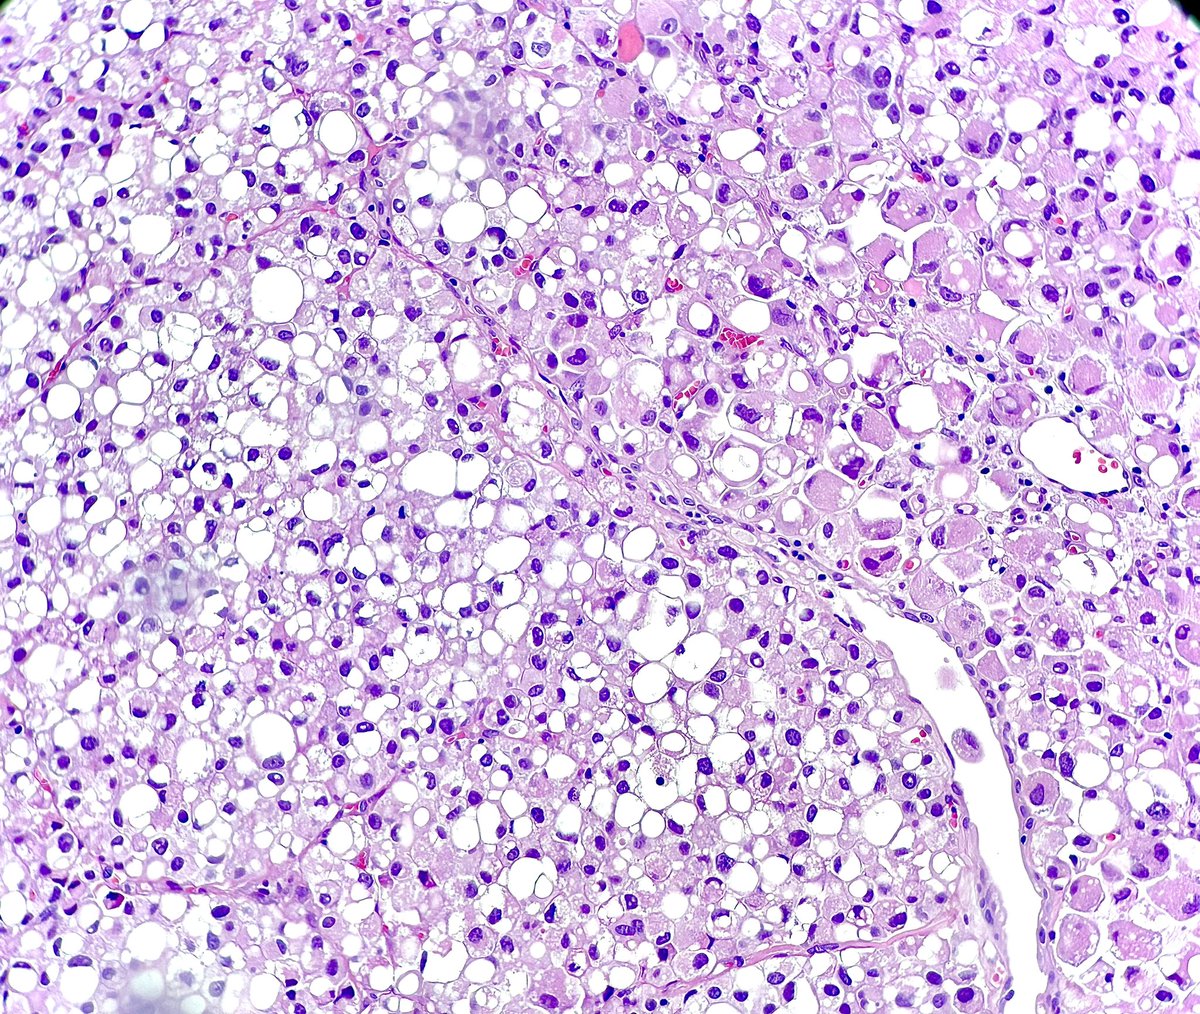

Lipid-rich urothelial carcinoma ✔️frequently associated with conventional urothelial carcinoma ✔️ lipid nature of the vacuolar content has been confirmed by EM ✔️ poor prognosis ✔️ + CK7, CK20 (photo), 34betaE12 #gupath #pathology #uropathology